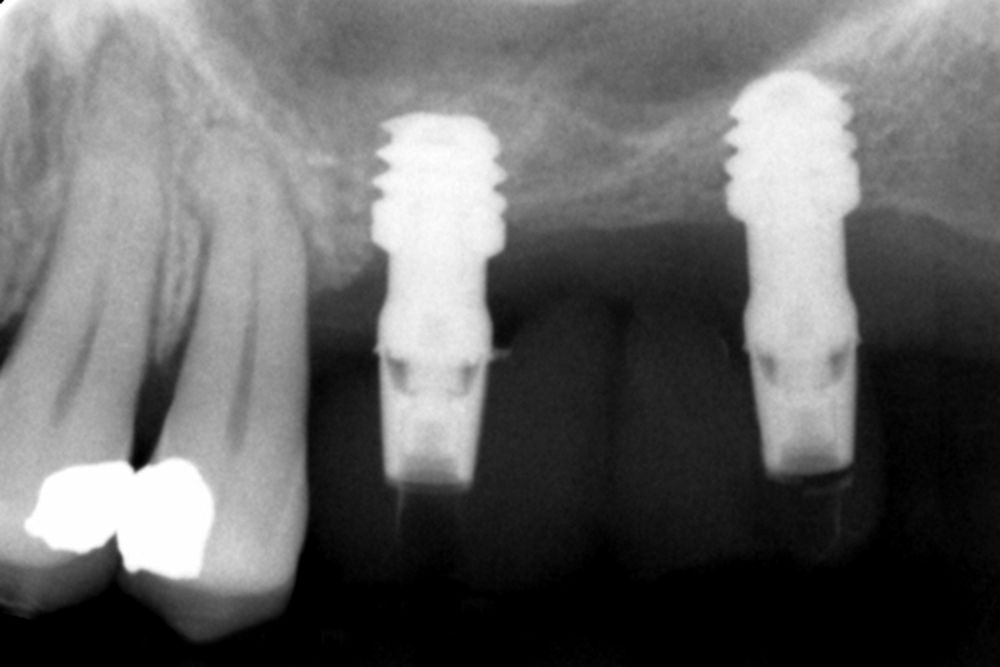

Material and method. A retrospective study has been carried out in patients in whom extra-short implants (4.5 and 5.5 mm length) were inserted directly by transcrestal elevation with residual ridges between 2 and 3 mm. The implant was the analysis unit for the descriptive statistics regarding location, implant dimensions, and radiographic measurements. The patient was the measurement unit for the analysis of age, sex and medical history. The main variable was the gain in height over the apex of the implant after 6 months of the surgery and one year after the load comparing both measurements and as secondary variables the biological complications and the implant failure were recorded.

Results. Ten patients who met the inclusion criteria were recruited and 20 implants were inserted. The mean residual bone volume height was 3.1 mm (+/- 0.3 mm with a range elevation above the apex of the implant in millimetres is of 2.8 mm (+/- 0.99 range 1.9 -5 mm). In the control cone-beam after one year of the studied load of the implants, the bone gain achieved was maintained, with no decrease in the volume gained, only three cases showed a decrease of between 0.4 and 0.5 mm of the initial volume at the end. No implants failed in the follow-up period and no biological complications were found in the surgery.

In this type of approach to the sinus, an important point is the stability of the grafted bone, located above the apex of the implant and with a bone tissue little vascularized (as usually occurs in these large atrophies with low density), so assessing what happens with the bone volume gained by this long-term procedure is also a key fact26,27. The mineralization of the bone graft and its maintenance once the implant loading is performed can make the difference in the success of the technique, especially in increasingly extreme cases. Therefore, the material used as a graft and the surface of the implant are two factors to take into account when performing this type of procedure28-31. Hydrophilic and osteoconductive surfaces in implants are of vital importance in these complex cases, as well as the filling materials that stimulate the formation of new bone28-31. The implants with UnicCa (Biotechnology Institute, Vitoria, Spain) surface, have a superhydrophilic surface. It is a very rough surface (Optima), with a calcium ions layer. This implies that the contact of blood and plasma with all points of the surface increases to the maximum the active surface for regeneration, by being completely coated with fluids due to its high capillarity. In the following series of clinical cases, patients treated by transcrestal sinus lift, with extra-short and ultra-short implants (4.5 and 5.5 mm), BTI (Biotechnology institute), of internal connection and universal plus platform in residual bone heights below 3 mm, studying the behaviour of implants regarding their survival as well as the maintenance of the bone volume achieved in the crestal elevation.